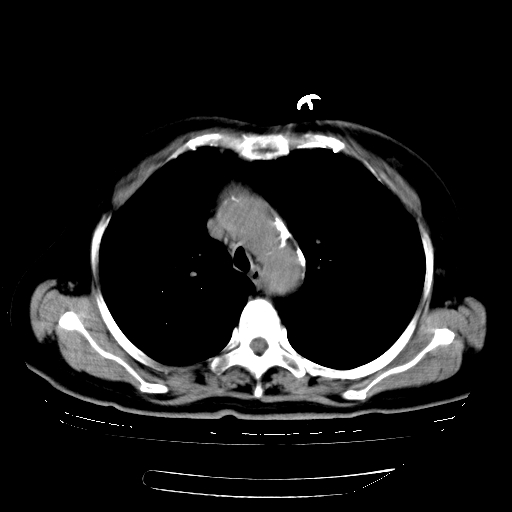

标题: CT23067:女,70岁,咳嗽、咳痰一个月,低热一周。 [打印本页]

女,70岁,咳嗽、咳痰一个月,低热一周。

1.左上肺结核,部分纤维化。右肺中下叶部分肺不张,内见液化、坏死及点状钙化,右中下叶支气管壁增厚、管腔狭窄,见多个点状钙化,结合临床考虑支气管内膜结核,建议痰检查抗酸杆菌并参考血沉。两肺多个小圆点状高密度灶,境界模糊,多考虑结核肺内播散。但本人年龄较大首先应支气管镜检以除外右肺癌。

2.胸主动脉夹层。

支持,首先一元论解释。胸主动脉部分层面环形低密度,中心强化。环形影不强化。不象真假腔的改变。我考虑动脉炎,不太支持夹层动脉瘤-和大家的观点不一致,希望楼主让患者再做个心血管的彩超吧。